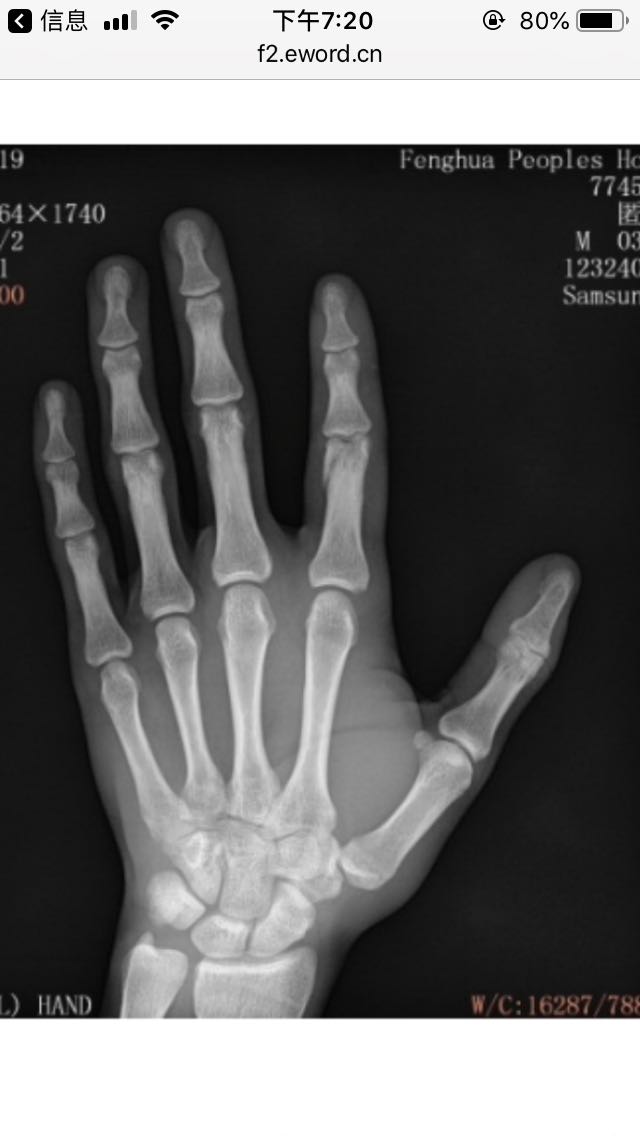

现在骨头这样子有必要继续开刀加钢片吗

位置看到了吧 在关节处 动的手术

这图骨头好端端的 爆开一点都要做吗

多了解下吧 骨折位置很关键 靠近关节的地方处理不好会有麻烦的